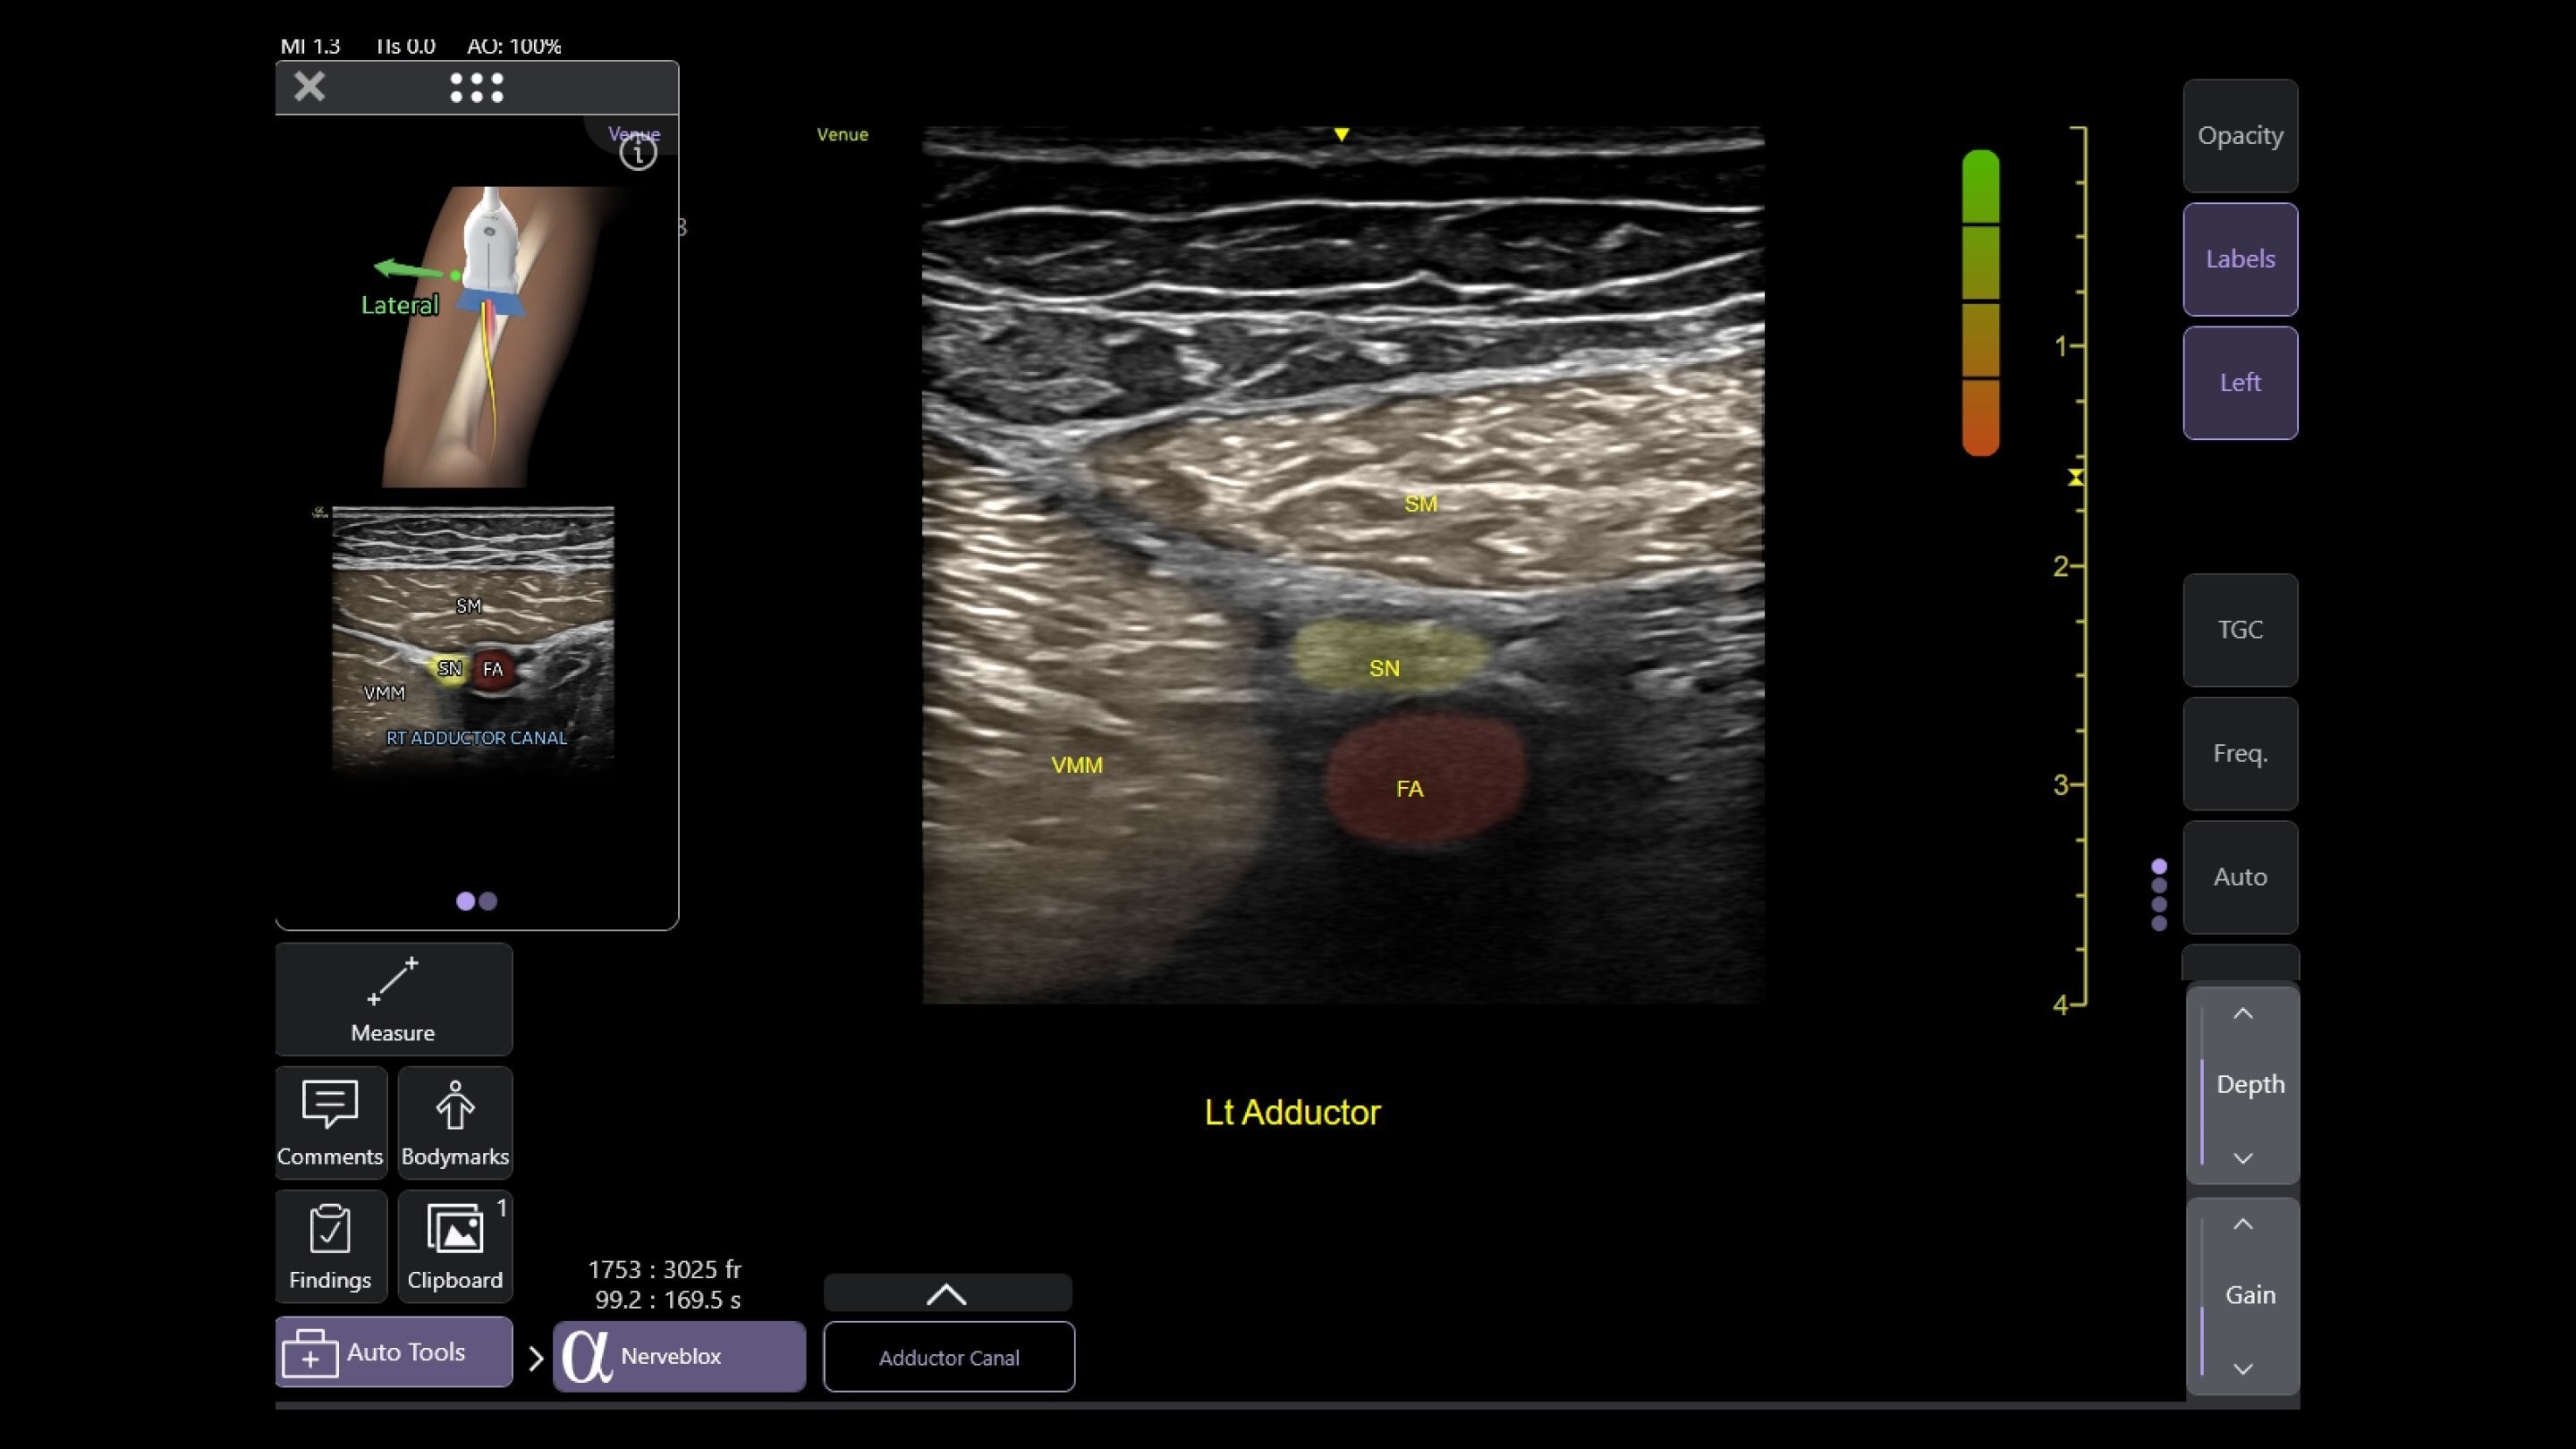

Wireless probe integration

Sync up and go - without wires you’re not tethered to a system or a space

Small yet powerful

Flexible, wireless dual-probes deliver clear images and Venue family software